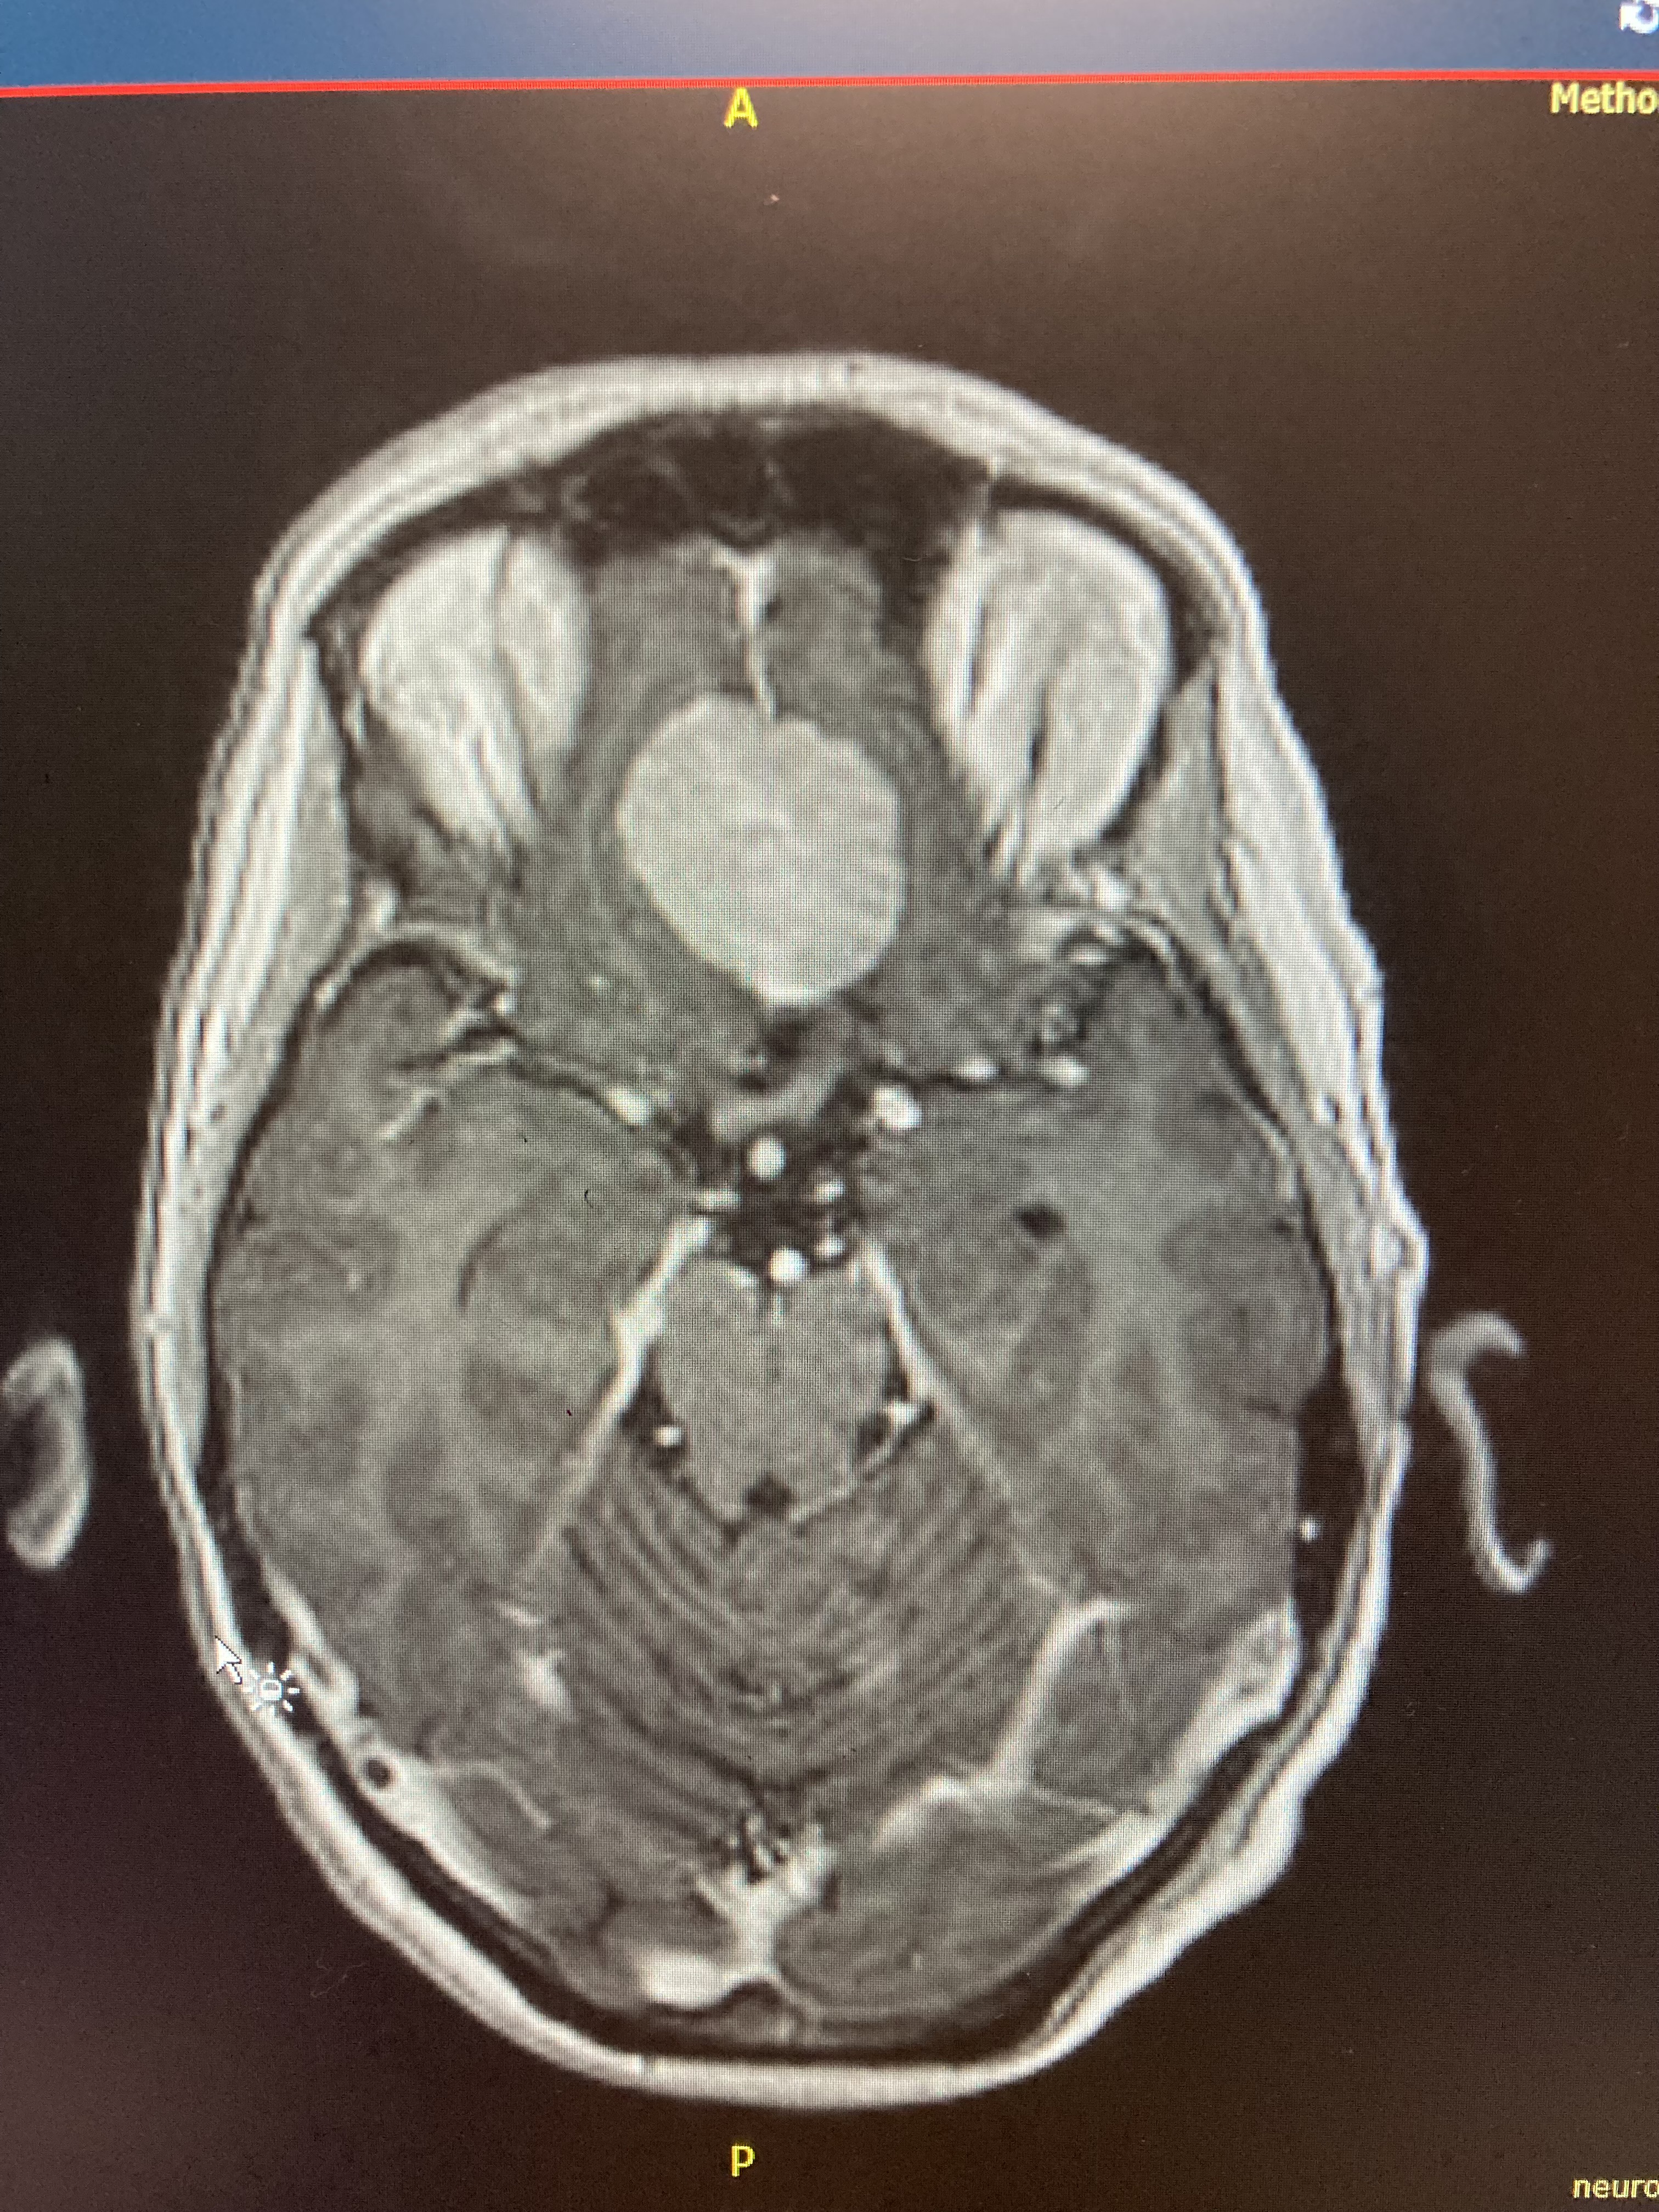

I was seen by two neurosurgeons the week after Vacation Bible school ended. It was then I learned more about the tumor, which was called a meningioma and was located at the base of my skull, under my brain, behind my eyes, and resting on the olfactory nerve. It was about 2.5 cm in diameter. Although most meningiomas are benign and slow-growing, because it was already causing symptoms, it needed to be removed. We scheduled surgery for early August because my retirement was planned for the end of July and there were some things I hoped to accomplish before then.

On the day of surgery I was called to the pre-op area where all the routine things like changing into a hospital gown, admission exam and paperwork, IV start, and visit with the anesthesiologist occurred. But there was a delay before surgery began because the neurosurgeon decided to take another image of the tumor to determine if he could use a different safer approach. A brain MRI with contrast was ordered and done. Although I had to wait an extra three hours to get started, the surgery was hopefully going to be significantly faster and less invasive than originally planned.